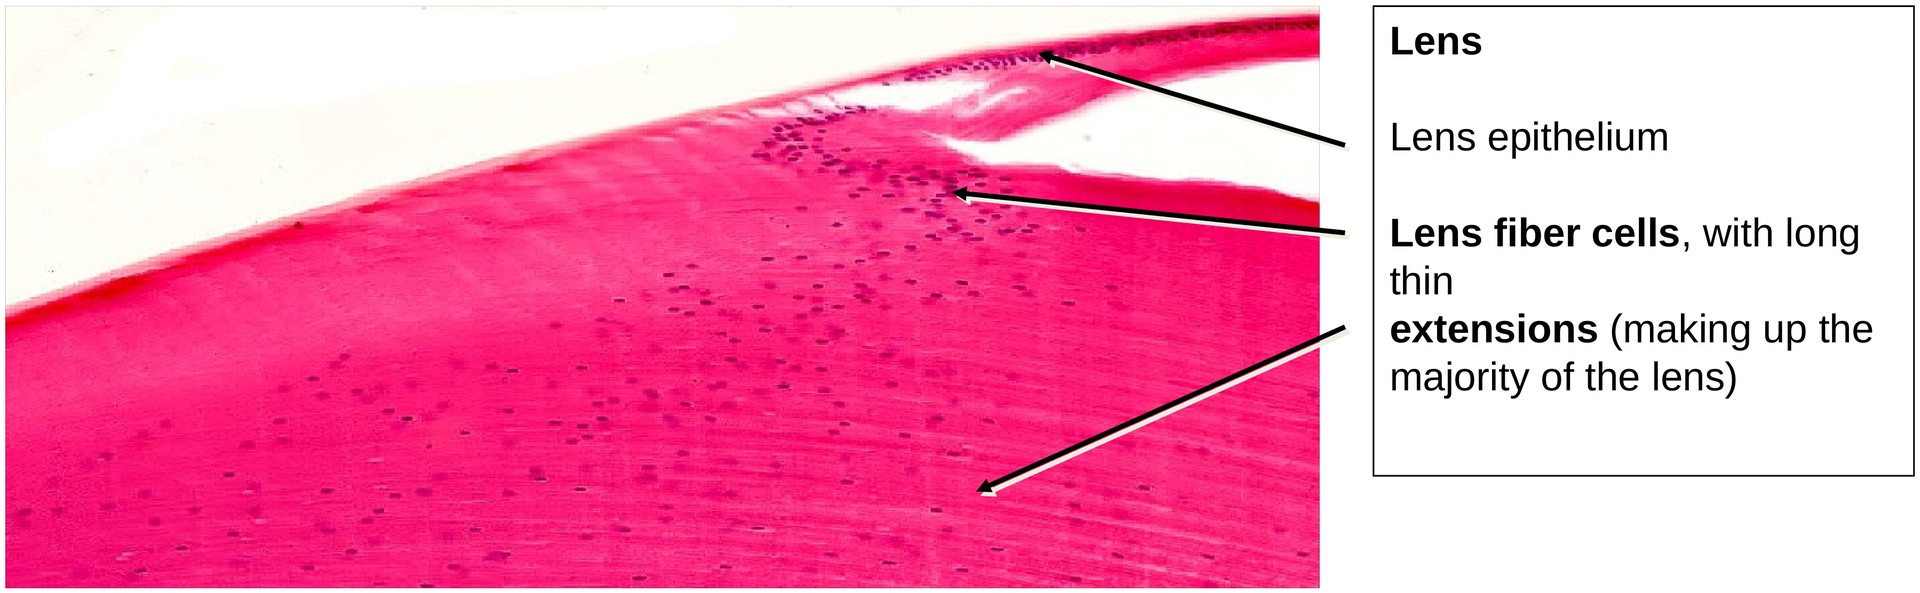

- What is meant by the term lens epithelium?

- Which structures make up the lens?